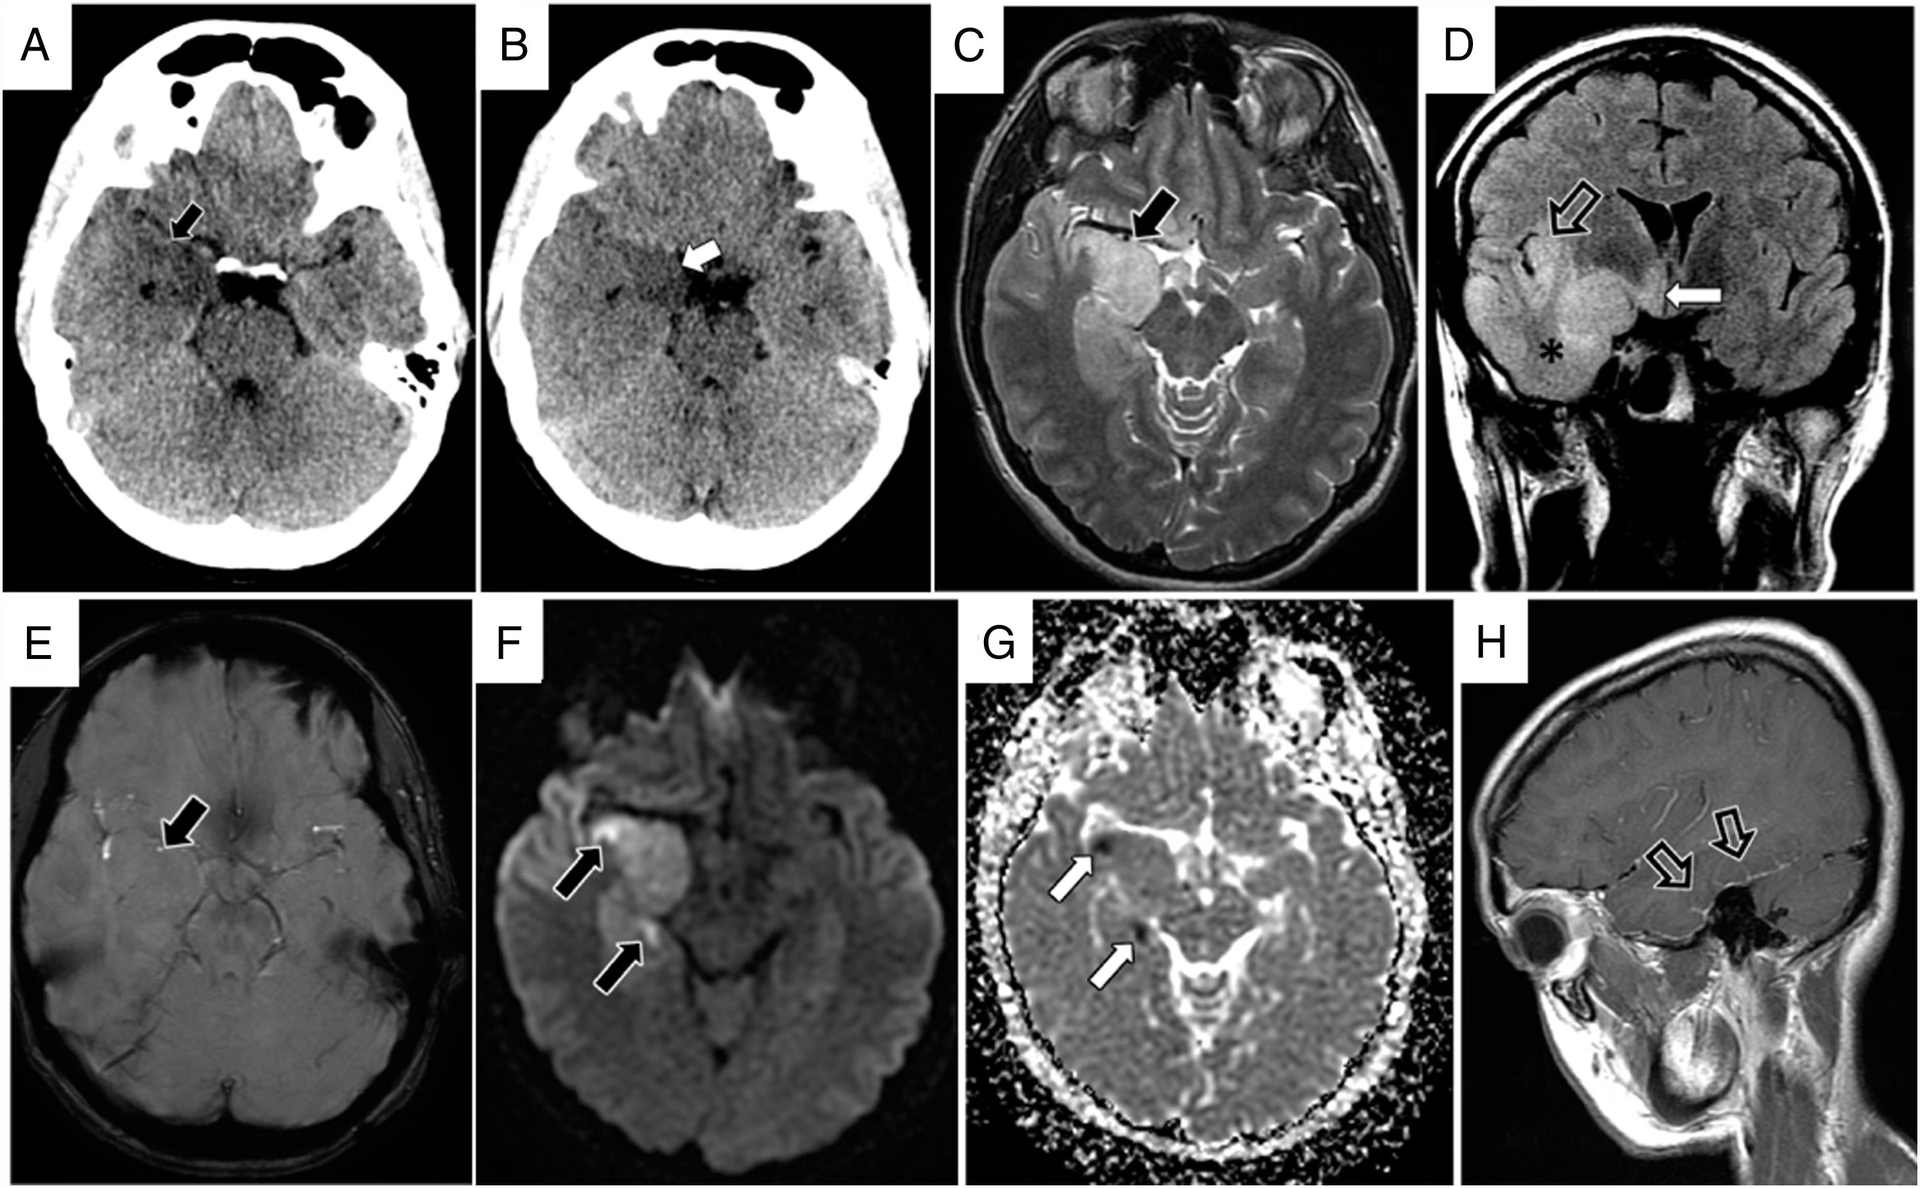

- Billeddiagnostik af Hjernen: En MR-scanning (Magnetisk Resonans) af hjernen er den foretrukne metode. Den kan vise tegn på inflammation, især i tindingelapperne (temporallapperne) og hippocampus, områder der ofte er påvirket ved denne type hjernebetændelse.